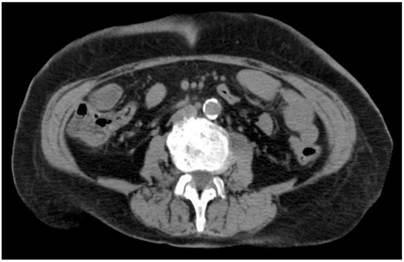

Por lo tanto, se realizaron paraclínicos con evidencia de leucocitosis (20,6 x 109 Cel/L) y neutrofilia (90 %). Debido a la sospecha de una perforación causada por el procedimiento realizado, se decidió practicar una tomografía de abdomen (Figura 2). En ella se observó un apéndice retrocecal de 11 mm, con alteración de la grasa adyacente, razón por la cual se efectuó una apendicetomía por laparoscopia.

La tomografía de abdomen se constituye en el estudio de elección para obtener un diagnóstico preoperatorio, en vista de que, como ya se refirió, la causa del dolor puede tener orígenes no quirúrgicos o estar relacionada con complicaciones más frecuentes. Por tanto, la tomografía de abdomen contribuye a establecer el manejo definitivo según los hallazgos.